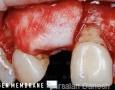

MEMBRANE:

Resorbable: Bio-Gide

Surgery